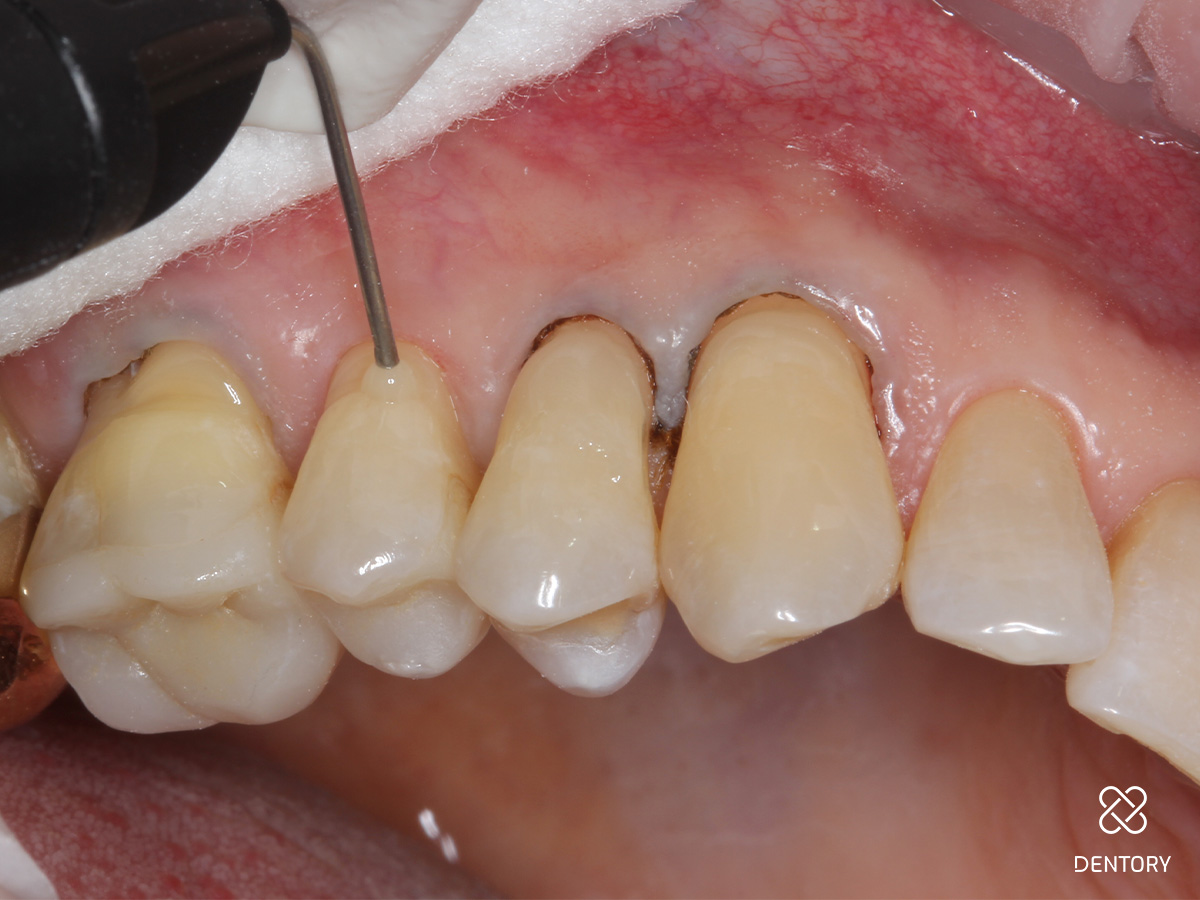

Abbildung 3

Zunächst Beläge und Biofilm sauber entfernen. Um eine Blutung des umgebenden Gewebes zu verhindern, wird ein Gingiva Schutzhalter angelegt. Das Instrument lässt sich schnell individuell anpassen und dem Zahnhals entsprechend formen. Die Gingiva wird leicht nach unten geschoben, um einen perfekten Sitz des Instrumentes zu garantieren.